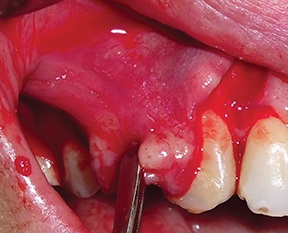

A full-thickness trapezoidal flap was elevated to expose the recipient site (Fig. 4). After releasing all muscular attachments, flap extension was checked coronally (Fig. 5).

Fig. 4: Intraoral view of the atrophic bone area

Fig. 5: Extent of flap release